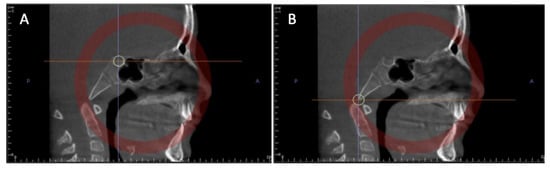

3.7.1. Photorealistic Visualization of Rendered CT Images